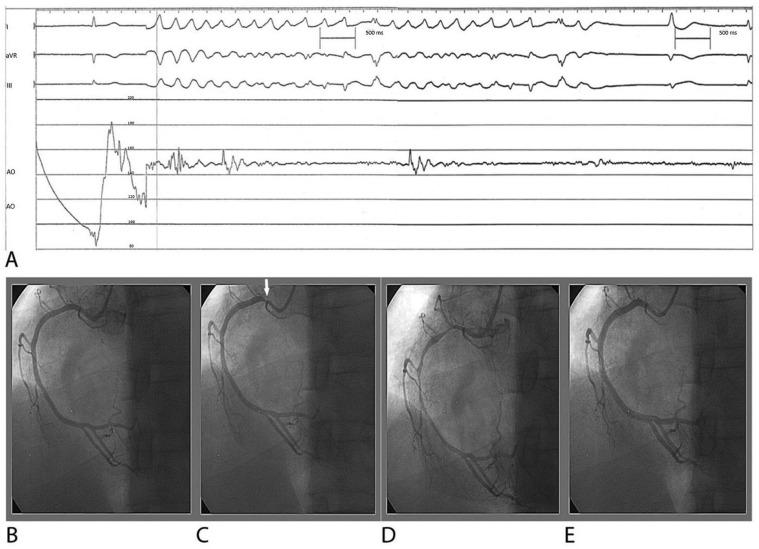

Although heart failure (HF) is a clinical syndrome that becomes worse over time, certain cases can be reversed with appropriate treatments. While coronary artery spasm (CAS) is still underappreciated and may be misdiagnosed, ischemia due to coronary artery disease and CAS is becoming the single most frequent cause of HF worldwide. CAS could lead to syncope, HF, arrhythmias, and myocardial ischemic syndromes such as asymptomatic ischemia, rest and/or effort angina, myocardial infarction, and sudden death. Albeit the clinical significance of asymptomatic CAS has been undervalued, affected individuals compared with those with classic Heberden's angina pectoris are at higher risk of syncope, life-threatening arrhythmias, and sudden death. As a result, a prompt diagnosis implements appropriate treatment strategies, which have significant life-changing consequences to prevent CAS-related complications, such as HF. Although an accurate diagnosis depends mainly on coronary angiography and provocative testing, clinical characteristics may help decision-making. Because the majority of CAS-related HF (CASHF) patients present with less severe phenotypes than overt HF, it underscores the importance of understanding risk factors correlated with CAS to prevent the future burden of HF. This narrative literature review summarises and discusses separately the epidemiology, clinical features, pathophysiology, and management of patients with CASHF.

尽管心力衰竭(HF)是一种随着时间推移而恶化的临床综合征,但某些病例可以通过适当的治疗得到逆转。虽然冠状动脉痉挛(CAS)仍然未被充分认识,并且可能被误诊,但由于冠状动脉疾病和 CAS 引起的缺血已成为全球 HF 的单一最常见原因。CAS 可导致晕厥、HF、心律失常和心肌缺血综合征,如无症状性缺血、静息和/或劳力性心绞痛、心肌梗死和猝死。尽管无症状性 CAS 的临床意义被低估,但与经典 Heberden 心绞痛患者相比,受影响的个体发生晕厥、危及生命的心律失常和猝死的风险更高。因此,及时诊断并采取适当的治疗策略,对预防与 CAS 相关的并发症(如 HF)具有重大的改变生活的意义。虽然准确的诊断主要取决于冠状动脉造影和激发试验,但临床特征可能有助于决策。由于大多数与 CAS 相关的 HF(CASHF)患者的表型比明显 HF 患者的表型更轻,因此强调了了解与 CAS 相关的风险因素以预防未来 HF 负担的重要性。本叙述性文献综述分别总结和讨论了 CASHF 患者的流行病学、临床特征、病理生理学和管理。